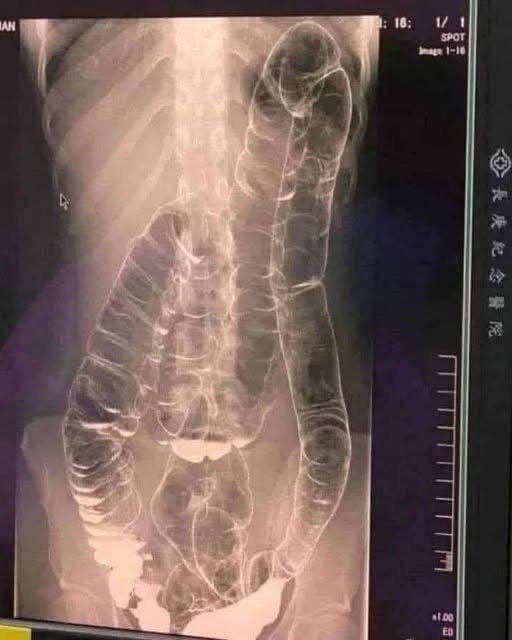

Entre los síntomas más habituales del estreñimiento se encuentran la sensación de evacuación incompleta, dolor o esfuerzo excesivo al defecar, hinchazón abdominal y una sensación constante de pesadez. Aunque muchas personas consideran que es un malestar pasajero, lo cierto es que cuando se vuelve crónico, puede dar lugar a complicaciones graves como hemorroides, fisuras anales, impactación fecal (una acumulación tan severa de heces que bloquea el colon o el recto), e incluso puede contribuir a desarrollar megacolon tóxico, una condición potencialmente mortal. Además, algunos estudios han vinculado el estreñimiento crónico con un aumento del riesgo de cáncer colorrectal, aunque aún se requiere más evidencia científica para confirmarlo con certeza.